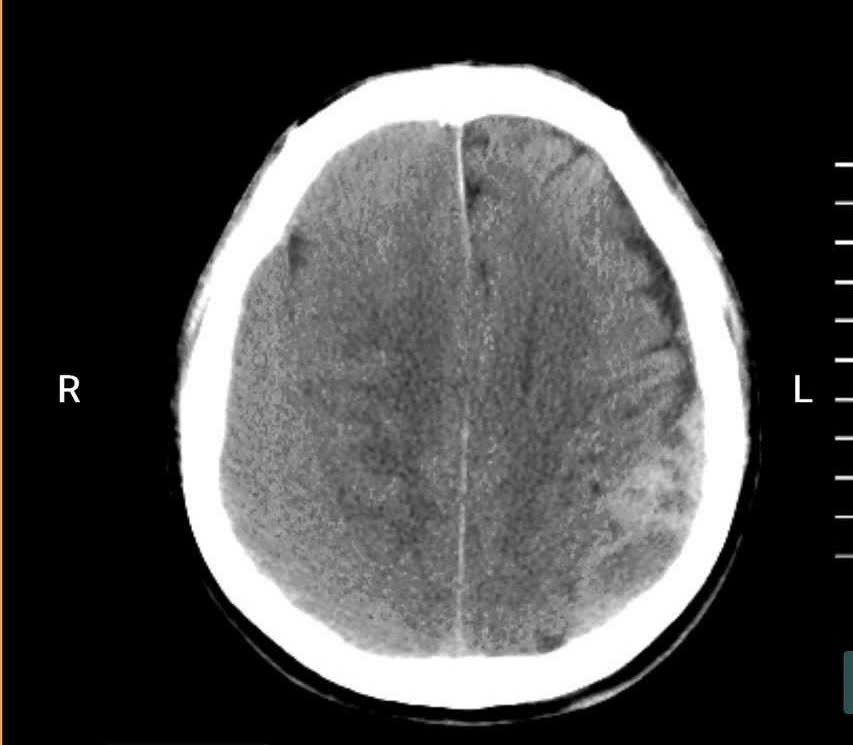

Qua thăm khám lâm sàng và thực hiện chụp cắt lớp vi tính sọ não, các bác sĩ phát hiện bệnh nhân bị tụ máu dưới màng cứng bán cấp hai bên với số lượng nhiều. Đây là tình trạng bệnh lý nguy hiểm, cần can thiệp phẫu thuật cấp cứu. Bệnh viện đã tổ chức hội chẩn với chuyên khoa Ngoại Thần kinh – Bệnh viện Đa khoa tỉnh Quảng Ninh, đồng thời hoàn thiện các xét nghiệm cần thiết và thống nhất chỉ định phẫu thuật lấy khối máu tụ trong sọ cho người bệnh.

Hình ảnh chụp cắt lớp vi tính sọ não